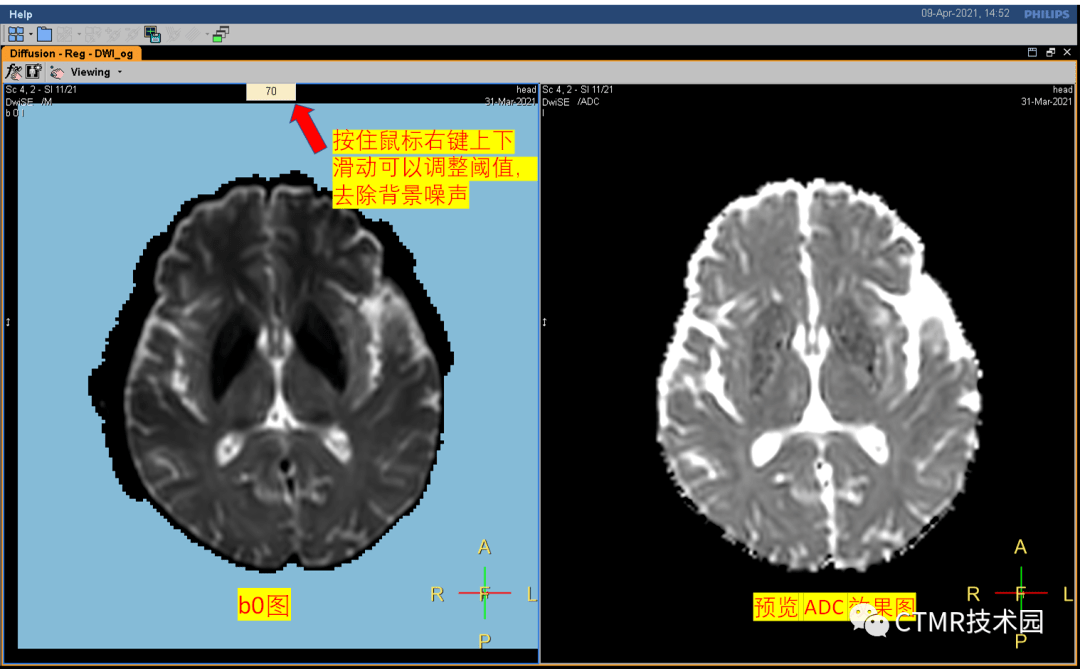

手把手教你基础颅脑mr平扫及后处理